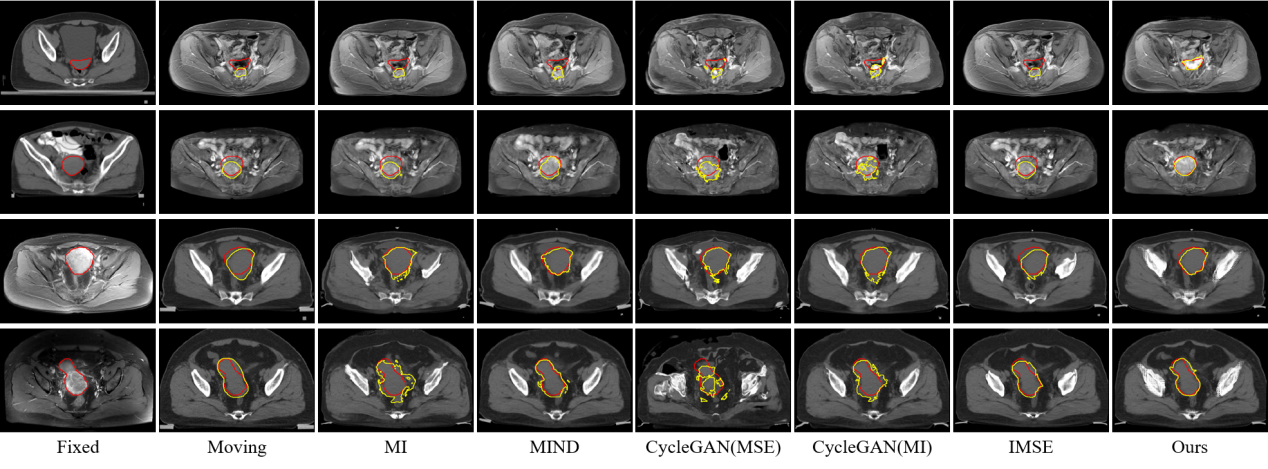

研究結(jié)果表明,SynMSE 在L2R 2022 CT-MR腹部數(shù)據(jù)集、臨床宮頸CT-MR數(shù)據(jù)集以及CuRIOUS MR-US腦數(shù)據(jù)集上均取得了最優(yōu)配準(zhǔn)性能。與傳統(tǒng)方法相比,SynMSE顯著提升了Dice系數(shù)、降低了HD95與TRE誤差,實(shí)現(xiàn)了在復(fù)雜模態(tài)差異下的高精度解剖結(jié)構(gòu)對齊。圖4-圖6分別為所提出方法在三個數(shù)據(jù)集上的定性結(jié)果展示,紅色標(biāo)注代表固定圖像的目標(biāo)器官區(qū)域,黃色標(biāo)注代表浮動圖像與配準(zhǔn)后圖像的目標(biāo)器官區(qū)域。表示圖中結(jié)果顯示,SynMSE更好的克服了多模態(tài)圖像間的復(fù)雜分布差異,不僅實(shí)現(xiàn)了更精確的配準(zhǔn)效果,而且有效保持了組織邊界與解剖拓?fù)涞耐暾裕黠@優(yōu)于現(xiàn)有方法。

圖4:所提出方法與現(xiàn)有方法在L2R 2022 CT-MR腹部數(shù)據(jù)集上的定性效果

圖5:所提出方法與現(xiàn)有方法在臨床宮頸CT-MR數(shù)據(jù)集上的定性效果